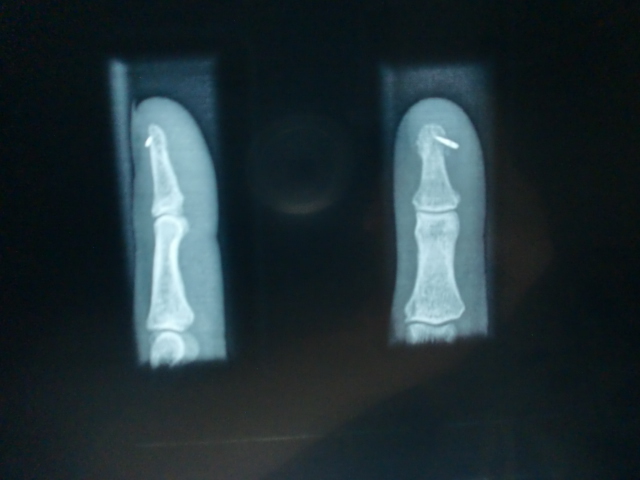

i aquest l'aspecte de les radiografies que em varen fer després de que 1 setmana d'antibiòtic no fes l'efecte esperat...

la foto de la radiografia no es veu gaire bé, però a l'original es pot veure fins i tot el forat de l'agulla...